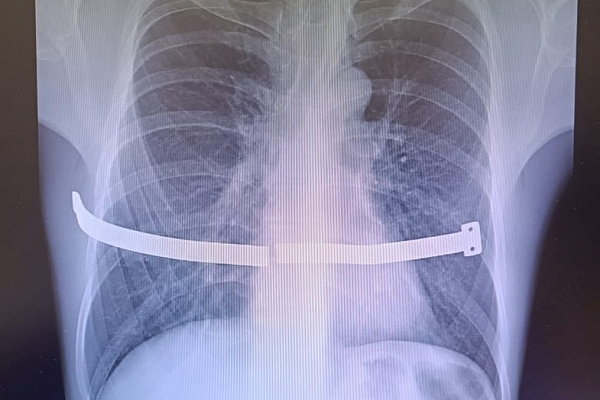

В хирургическое отделение Сургутской травмбольницы госпитализировали 33-летнего мужчину с отломками металлической пластины в грудной клетке. В своё время конструкцию ему установили для коррекции воронкообразной деформации груди. Устройство удаляют через 2-4 года. Как правило, этого периода достаточно для достижения эффекта. Но с операцией пациент не спешил, поскольку не испытывал никаких неудобств.

Пластину он носил 17 лет, пока та не разломилась пополам. Образовались острые и подвижные края. Один из них упирался в перикард – оболочку сердца. Из-за болевых ощущений мужчина вынужден был обратиться к врачам.